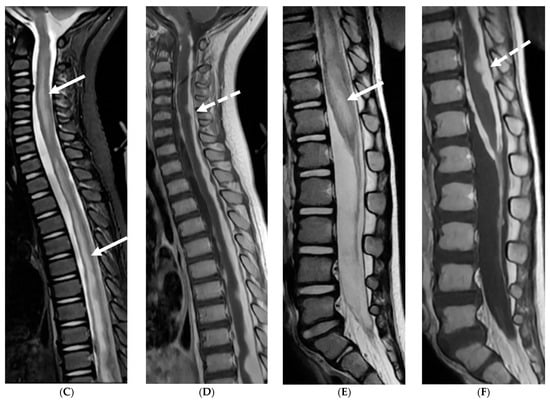

The most characteristic MRI findings in GBS are smooth contrast enhancement of the spinal nerve roots with variable thickening, particularly in the cauda equina region (Figure 4). Selective or prominent anterior nerve root enhancement favors the diagnosis of GBS [32,33]. A higher incidence of cranial nerve abnormalities, particularly the optic nerve, is seen in children with the GBS variant, Miller Fisher syndrome (MFS) [34,35]. Ultrasound imaging of peripheral nerves offers a promising new tool for early GBS diagnosis by detecting enlarged cervical nerve roots early in the disease course [36,37].

Figure 4.

Post contrast sagittal T1 (A) and axial T1 (B) of the lumbar spine, post contrast axial T1 of the brain (C,D): 14-year-old girl with numbness/tingling, paresthesia and bilateral lower extremity weakness. Patient also has bilateral facial weakness. There is diffuse mild thickening of the cauda equina nerve fibers with enhancement (arrows). Additionally, exiting nerve roots of the cervical and thoracic region also show enhancement. Enhancement of bilateral facial (dashed arrows) and trigeminal nerves is also visualized (curved arrows). Features are in keeping with Guillain-Barre syndrome (acute inflammatory demyelinating polyneuropathy). With involvement of facial and trigeminal nerves, Miller Fisher variant should be considered.